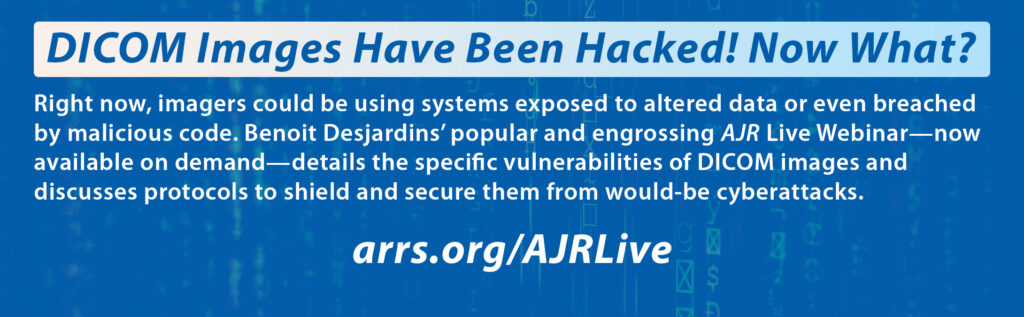

Our professional society reflects the same collective ethic. Our central belief hinges on having faith in the power of our collective. We hope to educate each other, support each other, and facilitate our collective progress, so that we may become the very best that we can be at what we do. It doesn’t matter if we have to convert the in-person ARRS Annual Meeting to an all-virtual convening, if we must distribute our educational materials in a more effective way, if we need to focus our practice communications on the realities of pandemic management, if we need to share fast-breaking scientific communications regarding COVID-19 to help you work better and smarter, or if we utilize our platforms and publications as a bridge to timely and essential topics, such as diversity in health care. This professional society tirelessly does what it has to do to inspire and empower you.